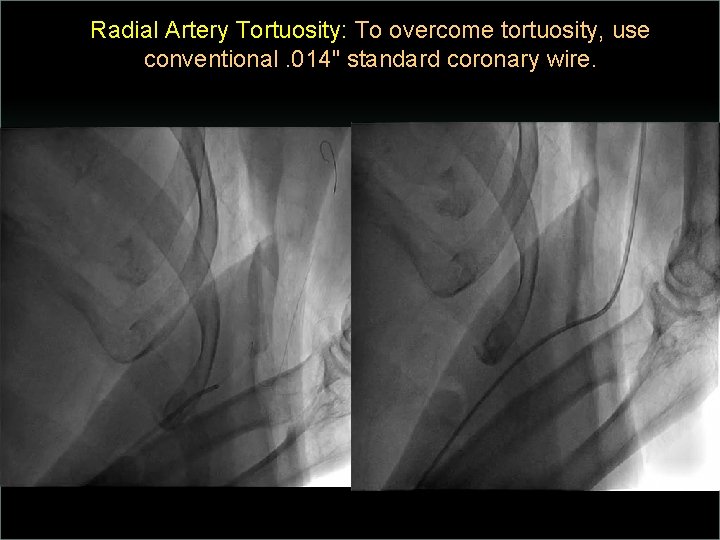

Transradial Interventions Difficult Anatomic Substrate Challenges and Solutions